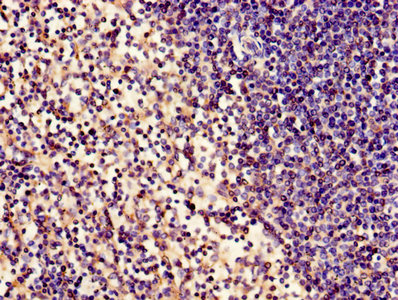

Immunohistochemistry of paraffin-embedded human spleen tissue using CSB-PA001094LA01HU at dilution of 1:100